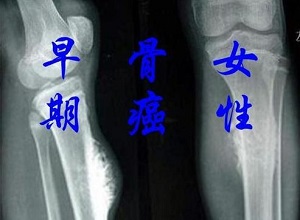

郑州肿瘤医馆排名:四个因素可能会引发骨癌。骨肿瘤是发生于骨骼或其附属组织的肿瘤。有良性,恶性之分。恶性骨肿瘤,就是大家常说的“骨癌”,其发展迅速,预后不佳,死亡率高。恶性骨肿瘤分为原发性和继发性。从体内其他组织或器官的肿瘤经血液循环、淋巴系统转移至骨骼为继发性恶性骨肿瘤。那么,骨癌是怎么引起的?

生活中容易引起骨癌的主要因,素是一切的电离辐射,像X线、镭、氢、锶、放射性同位素等,通过体内或体外进行放射,都会诱使骨癌的发生。而放疗过量,也能够促使骨肉瘤的出现,在临床上被称为放射后骨肉瘤。因此,这也是导致骨癌的重要因素。